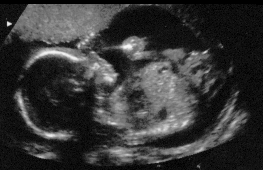

Here is a picture of my little face from my 7/1 ultrasound, at 20weeks and 1 day.

Profiles of me.